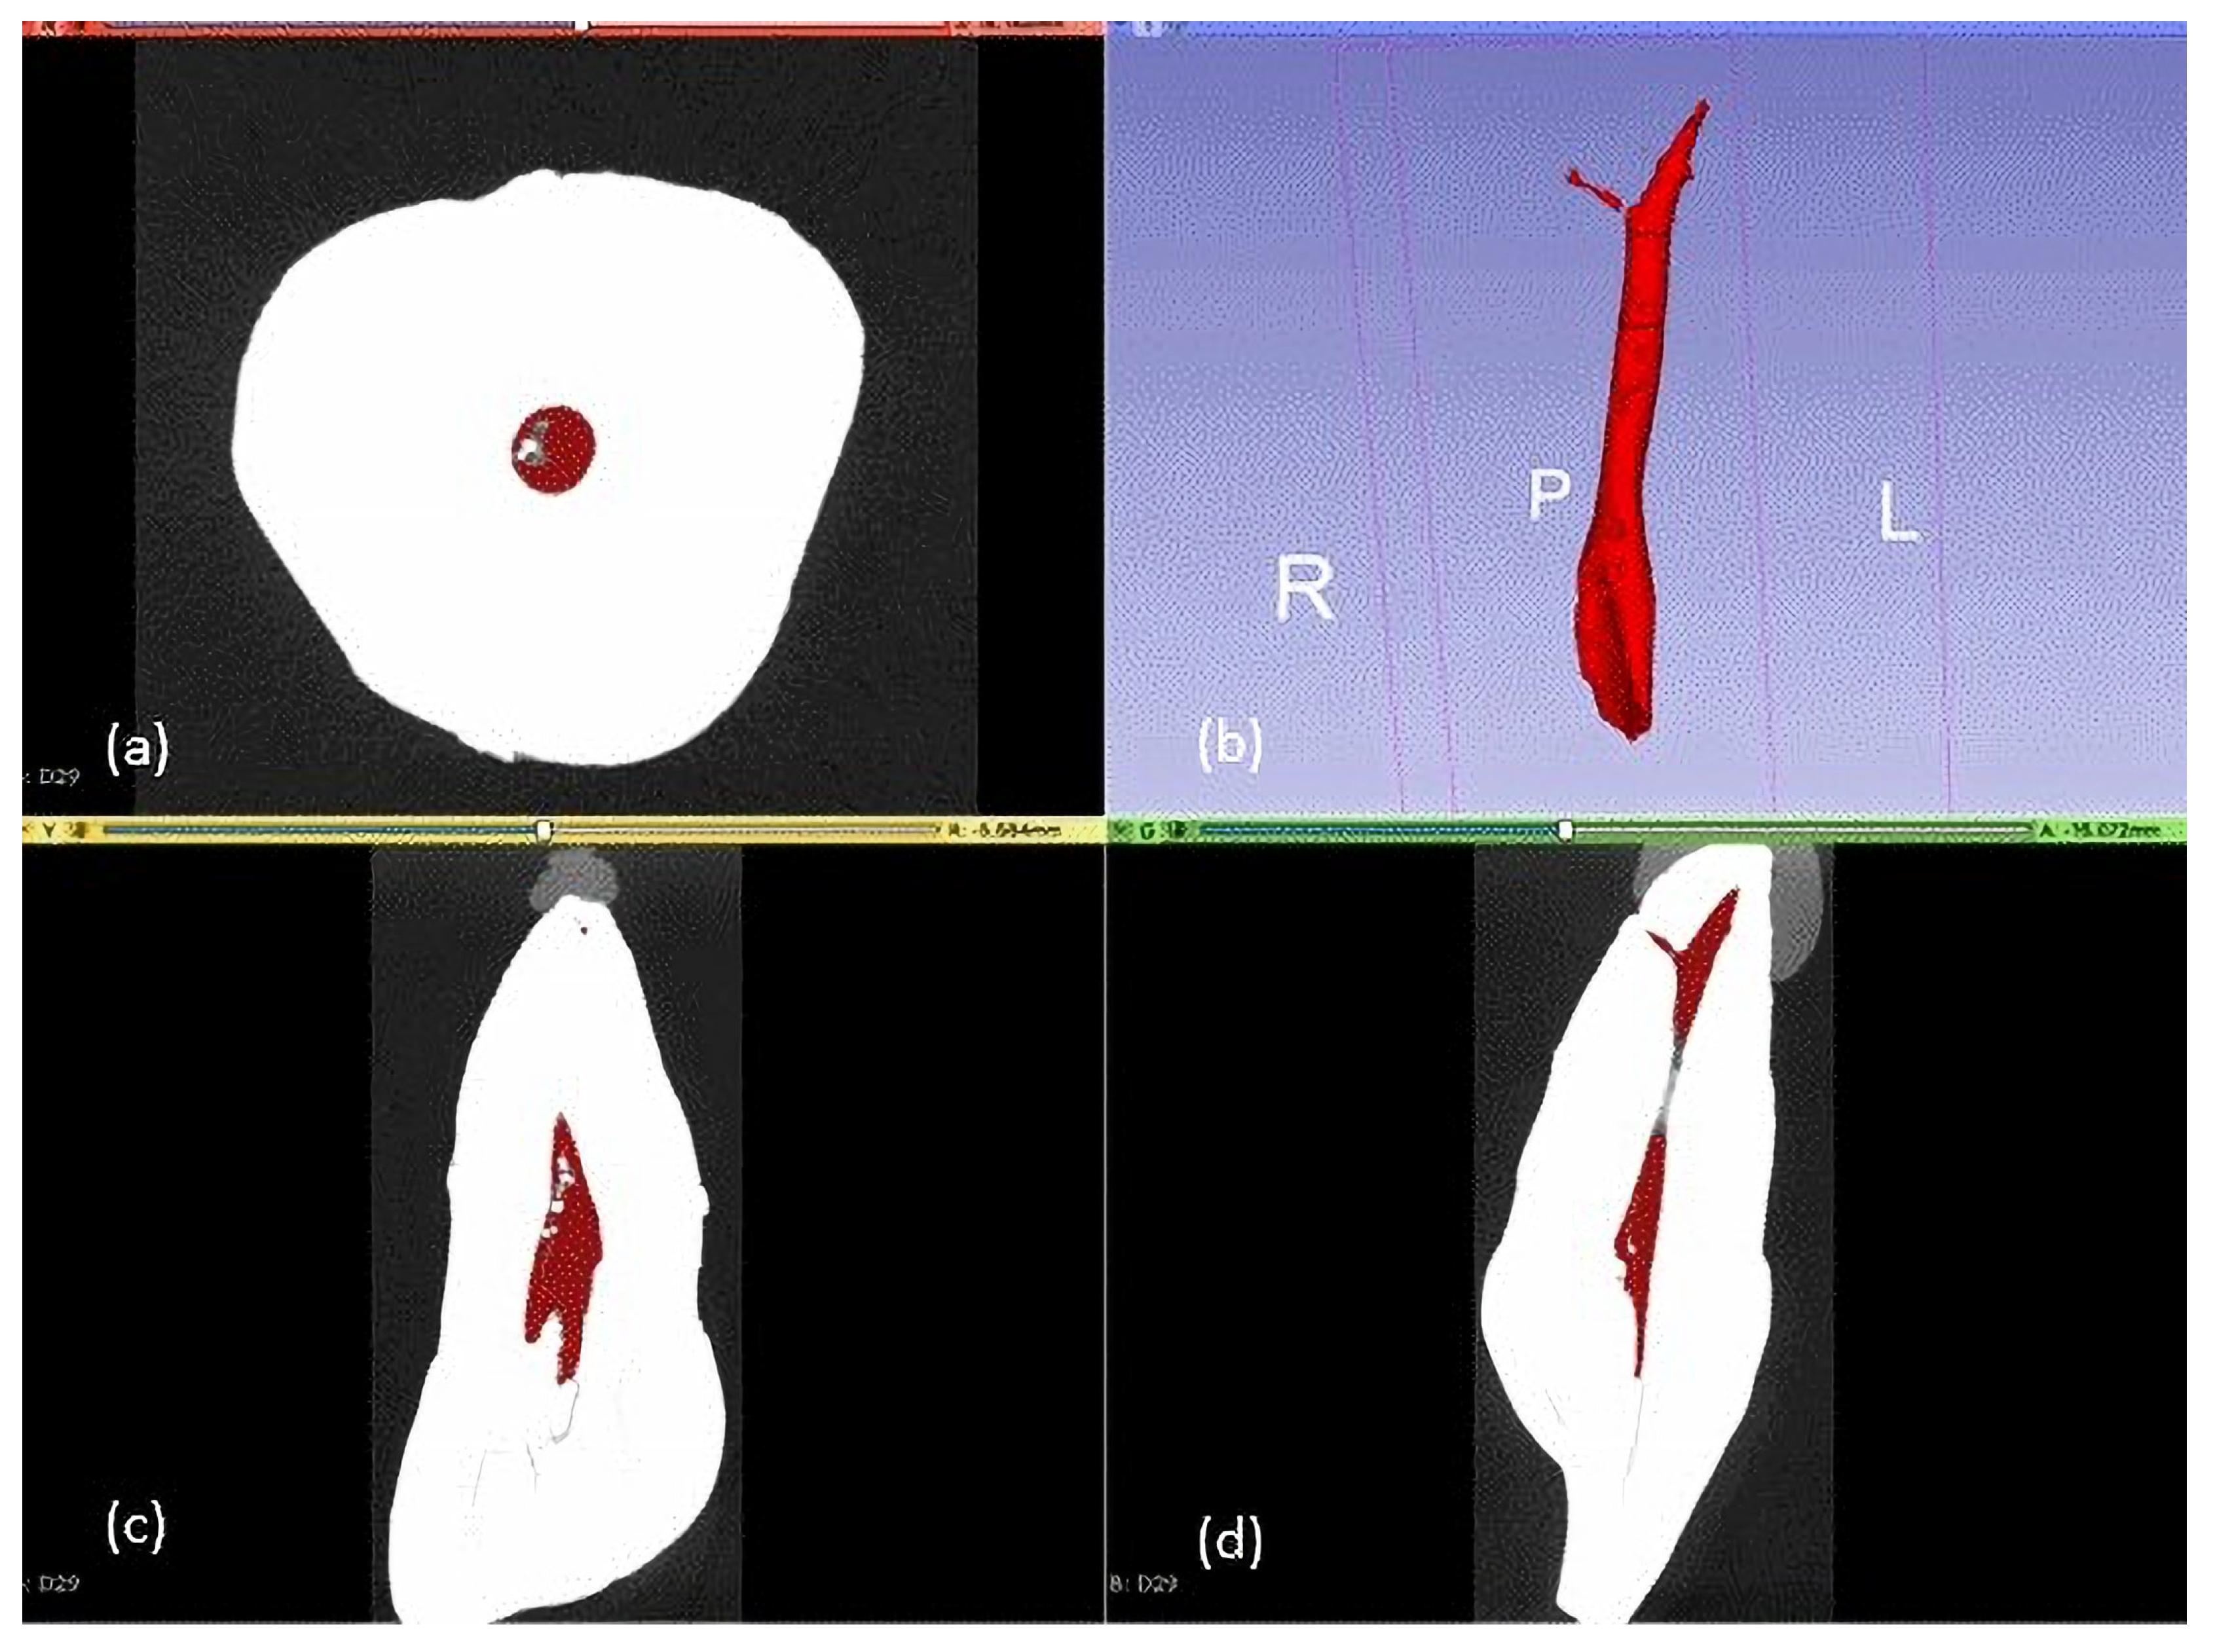

2.2. CBCT Study